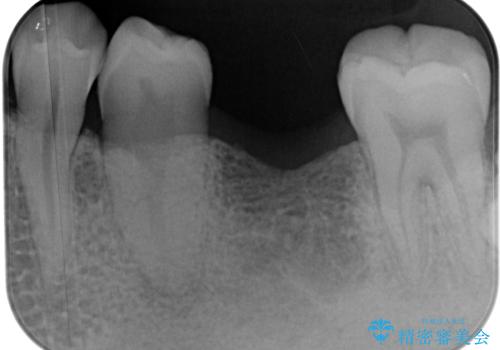

- 左下欠損部のインプラント治療を希望して来院された患者様です。

左下の欠損部を長期間欠損を放置していたことで、咬み合う上の奥歯が動いてしまっている状態でした。